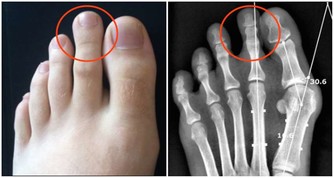

泌尿外科醫生不希望你:經常吃夜宵和火鍋

夜宵和火鍋中都會有大量的煎炸、辛辣食品,容易使前列腺長期充血,

尤其是吃夜宵和火鍋時喝點烈酒,酒精的刺激會加重前列腺充血的情況,容易引起前列腺炎。